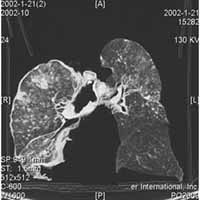

2.X線檢查 煤工塵肺胸片表現特徵有:網狀改變;結節狀改變;結節融合;塊狀陰影和多量絨毛狀改變。

網狀改變被認為是煤工塵肺最早的表現,在肺野呈現瀰漫性細網狀陰影。而此時在臨床上無任何症狀。隨著結節的擴展,病變融合成不透明的進行性大塊纖維化,通常位於兩肺上野,也可跨肺葉融合至中、下肺野,有時僅發生在一側肺野,通常為大塊狀,均勻的界限明顯的陰影。這些改變往往在單純性煤工塵肺彌散結節陰影的背景上發生。

在進行性大塊纖維化患者或有重度吸菸史者多合併有肺氣腫,嚴重肺氣腫往往致使肺部點狀和小結節顯示不清,易導致臨床醫生對病變估計不足。肺門淋巴結增大較少見。